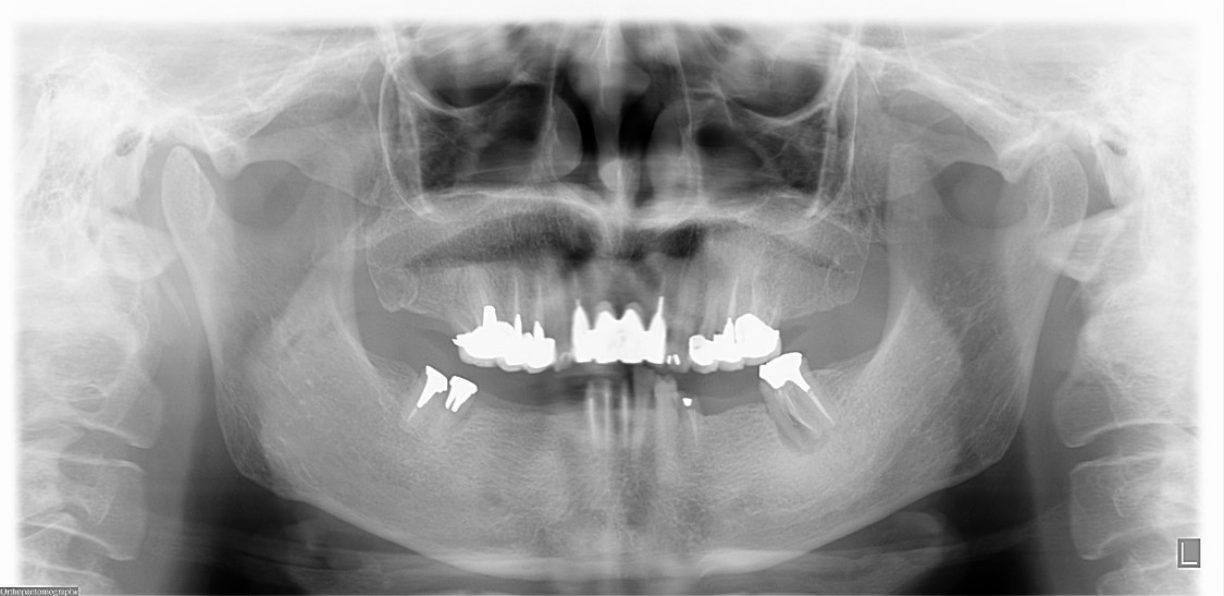

歯周病に罹患した患者さんのインプラント治療の症例②(うえだ歯科)

症例詳細

| 主訴 | 全顎治療希望、全顎的に歯が動く、奥の歯がなくて噛めない。できるだけ綺麗で噛めるようになりたい。 |

| 治療内容 | 全顎的に歯周病、前歯部の被蓋が深く、重度歯列不正が認められるため、 歯周外科を含む歯周治療、矯正治療、インプラント治療、セラミックによる補綴治療後メインテナンスに移行しました。 |

| 治療費 | 5,060,000円(税込)(インプラントすべて含む) |

| 治療期間 | 2年4ヶ月 |

| 治療回数 | 90回 |

| 想定されたリスク | 矯正治療の後戻り、歯周病の再発、食いしばり(パラファンクション)によるセラミックの破折、歯の破折のリスクがありました。 |